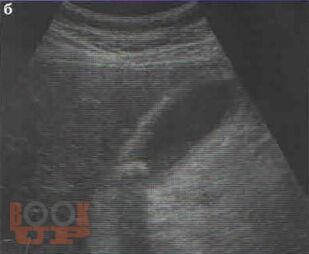

В учебном пособии представлена диагностика острого холецистита по данным ультразвукового исследования. Особое внимание уделено оценке положительных и отрицательных эхографических признаков острого холецистита на фоне проводимой терапии.